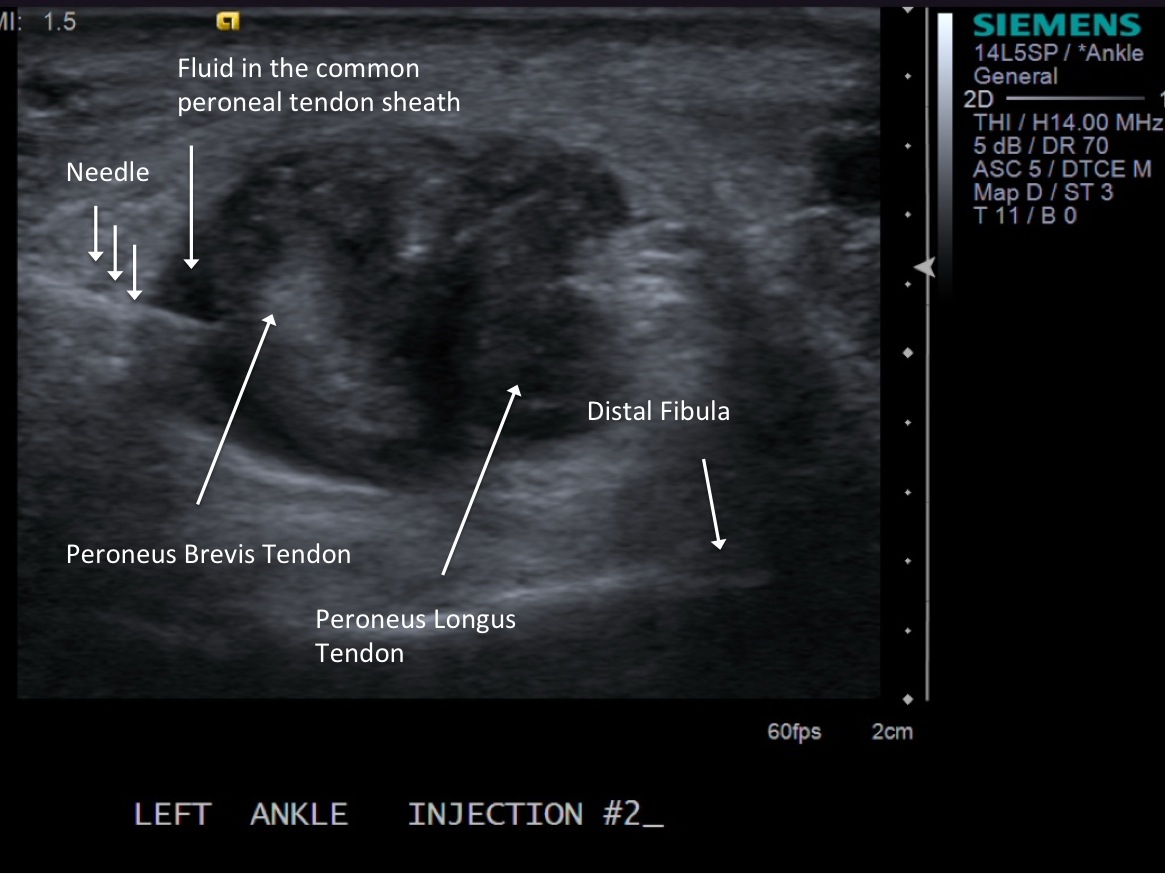

• 5cc syringe with 5cc of 1% Lidocaine

6. Inject 1% lidocaine superficially with 25g 1.5” needle. Advance needle deeper into the common peroneal tendon sheath.

• descriptiondescription